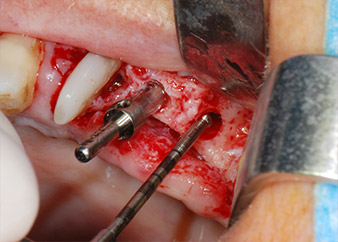

One month later, on the day of surgery, pain and inflammation at tooth 24 were minimal, but mobility of Miller class 2 was still present. After opening the flaps and cleaning the periapical and peri radicular infected tissue, the extent of the bone defect became obvious (Figs. 2 and 3).

At the buccal root, all vestibular and distal bone was missing. Attachment was essentially restricted to the palatal root, underlining the preliminary poor prognosis. Tooth 27 also showed a reduced horizontal attachment and a minimal apical rarefaction (cf. Fig. 1) without clinical symptoms.

total loss of bone and attachment

Fig. 2 and 3: After raising flaps, one month after endodontic revision and initiation of full-mouth periodontal therapy, the buccal root of tooth 24 showed a total loss of bone and attachment.

Implant beds were prepared at sites 25 and 26 with rotary instruments, used in a contra-angle handpiece with a 20 : 1 transmission ratio with an updated powerful implant motor (Implantmed, W&H) (Fig. 8).

The final preparation next to the sinus was again carried out with a piezoelectric instrument (Piezomed, insert S2).